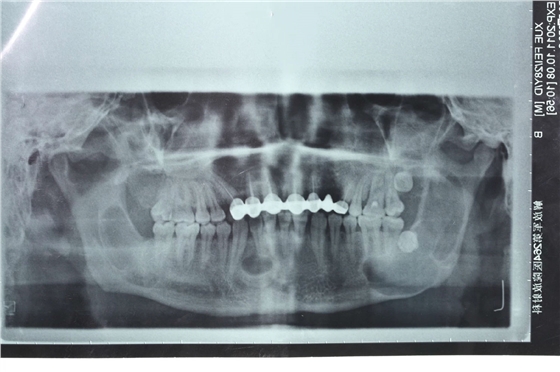

患者男性,主因左面部反復腫脹半年余,就診后行全景片檢查,發(fā)現(xiàn)下頜骨多發(fā)性囊腫,初步診斷為多發(fā)性頜骨囊腫綜合征,安排住院手術。